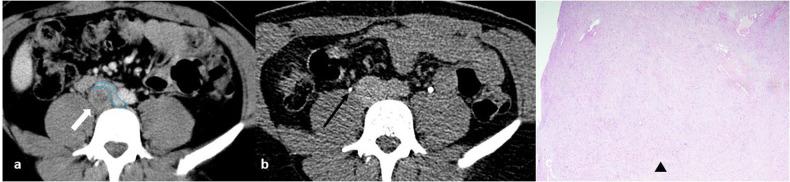

Benign nerve sheath tumors presenting as solitary retroperitoneal masses (RBNSTs) pose a complex diagnostic challenge for multidisciplinary teams regarding differential diagnosis, staging, and treatment planning. This article reviews the role played by different imaging techniques in assessing RBNSTs and elucidates their typical pathological features with a particular emphasis on the correlation between imaging and histological findings. Furthermore, some examples of retroperitoneal tumors that merit consideration in the process of differential diagnosis based on cross-sectional investigations (CSIs) are reported. The correlation between tissue architecture and appearance on imaging can help increase the accuracy of differential diagnosis with other retroperitoneal neoplasms at CSIs.

表现为孤立性腹膜后肿块的良性神经鞘瘤(RBNSTs)对多学科团队在鉴别诊断、分期和治疗规划方面构成了复杂的诊断挑战。本文回顾了不同成像技术在评估RBNSTs中所起的作用,并阐明了其典型的病理特征,特别强调了成像与组织学结果之间的相关性。此外,还报告了一些在基于横断面检查(CSI)进行鉴别诊断过程中值得考虑的腹膜后肿瘤实例。组织结构与成像表现之间的相关性有助于提高CSI时与其他腹膜后肿瘤鉴别诊断的准确性。